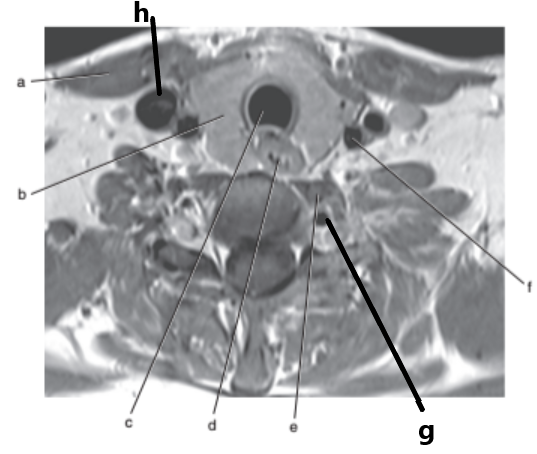

Vertebral artery

What is letter a ?

Internal jugular vein

What is letter f ?

Spinal cord

What is letter h ?

What is letter g ?